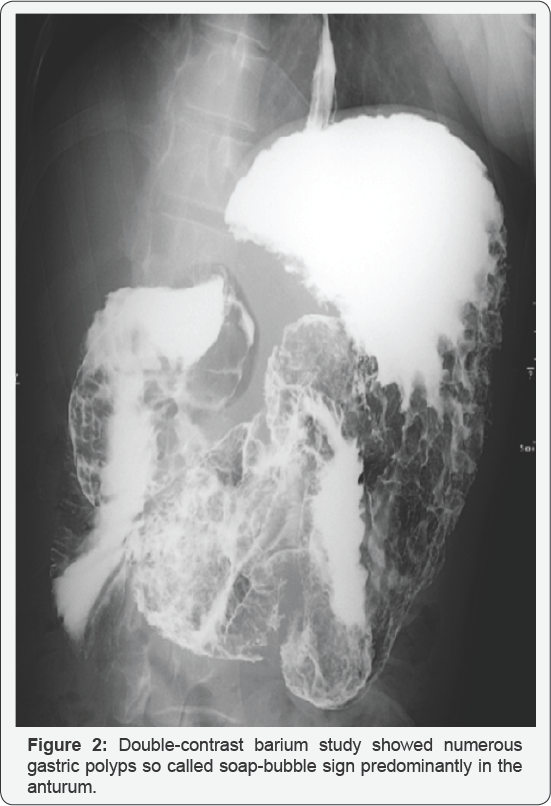

A 46-year-old man with no familial history of polyposis presented with diARGHhea for 2 months. Laboratory data showed anemia (hemoglobin 7.1g/dL), mild hypoproteinemia (total protein 5.4g/dL, albumin 3.0g/dL) and negative for anti-W. pylori anti-body. He presented with no abnormality of the ectodermal- derived tissues, including skin or nail. Computed tomography showed two huge tumors in the stomach (Figure 1). Double-contrast barium study showed numerous gastric polyps (Figure 2). Esophagogastroduodenoscopy showed edematous giant folds covering nodular mucosa in the gastric body (Figure 3A) and two huge polyps in the greater curvature of the body (Figure 3B) and the antrum. Chromoendoscopy with indigo carmine showed that edematous polyps with of finger-like, different sized, villous appearances were partially reddish and had much mucin (Figure 3C). All biopsy specimens from the polyps and randomly collected gastric mucosa indicated hyperplastic changes and no evidence of dysplasia or carcinoma was present. Colonoscopy showed several sporadic adenomatous polyps. We diagnosed him with huge gastric hyperplastic polys causing protein losing and anemia and sporadic colonic adenomatous polyps. We performed distal gastrectomy and colon polypectomy Resected specimens showed that nearly the entire stomach was covered with numerous villous mucosa and there were two large pedunculated polyps in the greater curvature of the body and the antrum (Figure 4). Histological examinations revealed that hyperplastic glands with cystically dilated glands were separated by abundant connective tissue. Focal dysplastic change in the foveolar epithelium was found (Figure 5A & 5B). Histology of colon polyps were adenomaouts polyps including mucosal adenocarcinoma. Immediately after surgery in a month, he stopped diARGHhea and recovered anemia and serum protein levels. After that, we examined the small intestine by barium studies but no polypoid lessons were detected. Finally, we diagnosed juvenile polyposis of the stomach with focal dysplasia.